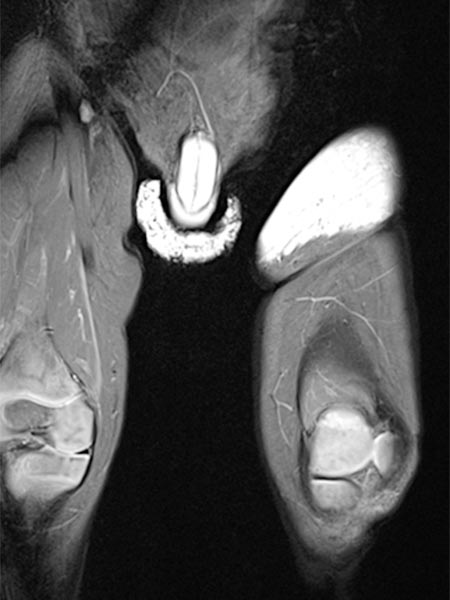

Die koronare, T2-gewichtete, fettgesättigte MRT zeigt den Tumor in der linken Leiste homogen stark hyperintens (13. Lebensmonat) und klar solide. Nebenbefundlich die durchnässte Windel, ebenfalls mit hoher Signalintensität.

Gleiche MRT-Sequenz, koronare Schichtführung. Der Tumor liegt nicht nur epifaszial, sondern zeigt auch eine geringe Ausdehnung nach subfaszial unter die Fascia lata in die Glutealmuskulatur. Damit klar infiltratives Verhalten.

Auch in der axialen Schichtführung der MRT (T2-gewichtet, fettgesättigt) ist die Infiltration der Muskulatur durch die Raumforderung gut dargestellt. Auch Hämangiome können als vaskuläre Tumoren eine solche Infiltration aufweisen, ohne dass sie maligne sein müssen.

In der nativen koronaren T1-gewichteten MRT ist der Tumor isointens zur Muskulatur ohne enthaltene Fettgewebsanteile. Er ist somit in dieser Sequenz kaum von der Muskulatur abgrenzbar.

Die axiale T2-Wichtung ohne Fettsättigung zeigt den Tumor homogen nur gering hyperintens. Er ist zwar hyperintenser als Muskulatur, aber insgesamt deutlich weniger hyperintens als das umgebende subkutane Fettgewebe.